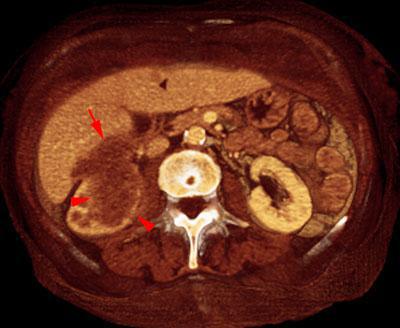

Metástasis renal de carcinoma broncopulmonar

VR seccional. Visión axial caudal. Metástasis en polo renal inferior derecho (puntas de flecha) con infiltración de fosa hepatorrenal y lóbulo hepático derecho (flecha)